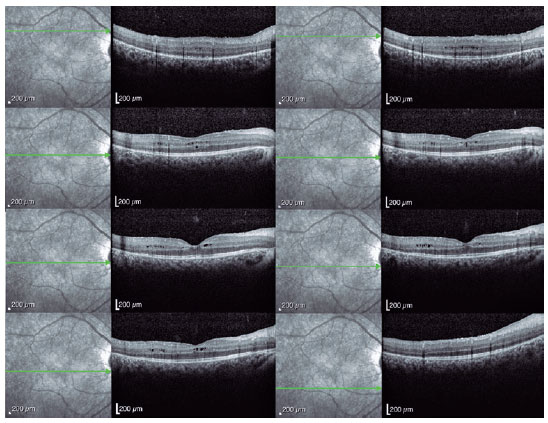

Spectral-domain optical coherence tomography (Spectralis, Heidelberg Engineering GmbH, Heidelberg, Germany) revealed a bilateral cystoid macular edema that was most prominent in the left eye (Figures 3 and 4). Genetic screening revealed heterozygous variants in the CRB1 gene (c.2843G>A and c.2506C>A), confirming the diagnosis of RP. The patient´s intraocular pressure (IOP) remained high, despite maximum medical treatment and the angle remained closed despite YAG laser iridotomy. Trabeculectomy was performed in the left eye to achieve adequate IOP control.

03-fig04.jpg)